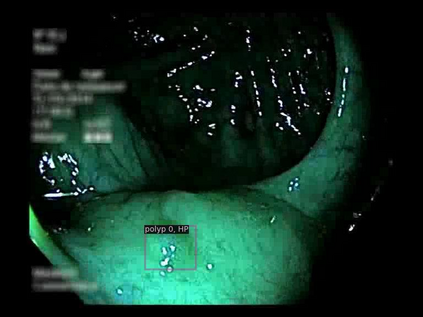

Early detection, accurate segmentation, classification and tracking of polyps during colonoscopy are critical for preventing colorectal cancer. Many existing deep-learning-based methods for analyzing colonoscopic videos either require task-specific fine-tuning, lack tracking capabilities, or rely on domain-specific pre-training. In this paper, we introduce \textit{PolypSegTrack}, a novel foundation model that jointly addresses polyp detection, segmentation, classification and unsupervised tracking in colonoscopic videos. Our approach leverages a novel conditional mask loss, enabling flexible training across datasets with either pixel-level segmentation masks or bounding box annotations, allowing us to bypass task-specific fine-tuning. Our unsupervised tracking module reliably associates polyp instances across frames using object queries, without relying on any heuristics. We leverage a robust vision foundation model backbone that is pre-trained unsupervisedly on natural images, thereby removing the need for domain-specific pre-training. Extensive experiments on multiple polyp benchmarks demonstrate that our method significantly outperforms existing state-of-the-art approaches in detection, segmentation, classification, and tracking.